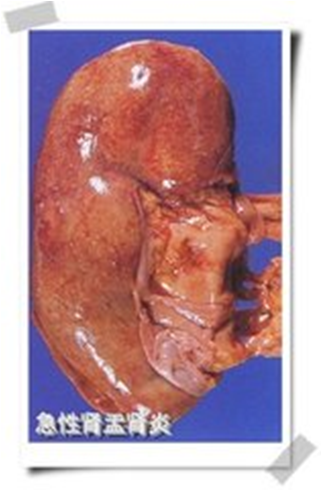

急性肾盂肾炎可单侧或双侧肾脏受累,表现为局限或广泛的肾盂肾盏黏膜充血、水肿,表面有脓性分泌物,黏膜下可有细小脓肿,于一个或几个肾乳头可见大小不一、尖端指向肾乳头、基底伸向肾皮质的楔形炎症病灶。病灶内可见不同程度的肾小管上皮细胞肿胀、坏死、脱落,肾小管腔中有脓性分泌物。肾间质水肿,内有白细胞浸润和小脓肿形成。炎症剧烈时可有广泛性出血,较大的炎症病灶愈合后局部形成瘢痕。肾小球一般无形态学改变。合并有尿路梗阻者,炎症范围常广泛。